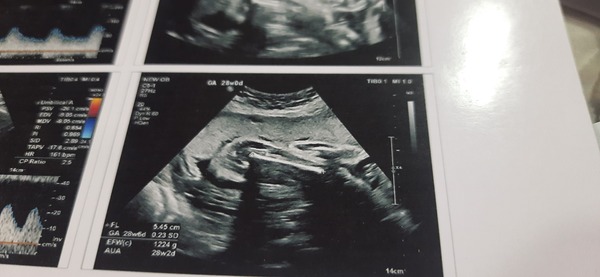

Any one gusse my one🙂 .NT scan and anomaly scan

Hi ladies . picture of my baby 28 week ultrasound any gusse gender of my little one😄